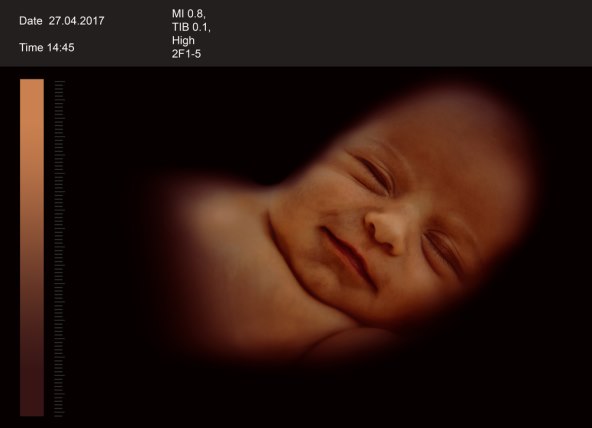

U 25. tjednu sazrijeva bebin sluh. Svaka je buduća majka to već doživjela: uključi li se mikser ili se zalupi vratima od auta, beba u trbuhu se trgne. Bebe u trbuhu rano mogu razlikovati „loše“ od „dobrih“ zvukova. Majčini znakovi ljubavi uvijek su dobrodošli: kada se majka obraća svojoj bebici u trbuhu, ona se umiri i veselo vrpolji. Profesor Manfred Hansmann godinama je proučavao koliko su buduća majka i dijete u njezinu trbuhu povezani: „Zamolim žene da nakon pregleda ultrazvukom još malo ostanu ležati i da glasno razgovaraju s djetetom. Pogledam li netom nakon toga ponovno na monitor, većina beba vrlo opušteno pliva maternicom. Smiruje se frekvencija bebina pulsa, ponekad tu opuštenost čak mogu primijetiti na bebinim crtama lica.“